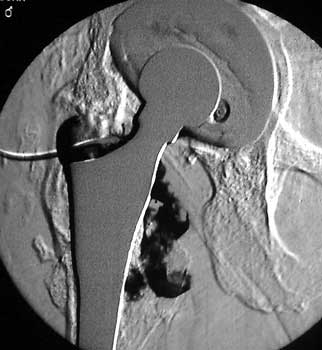

Dry tap secondary to large greater trochanteric bursa, 20

gauge spinal needle placed in bursa under fluoroscopic guidance

Scar with focal area of drainage. Dry tap secondary to large greater trochanteric bursa with

sinus tract draining to skin